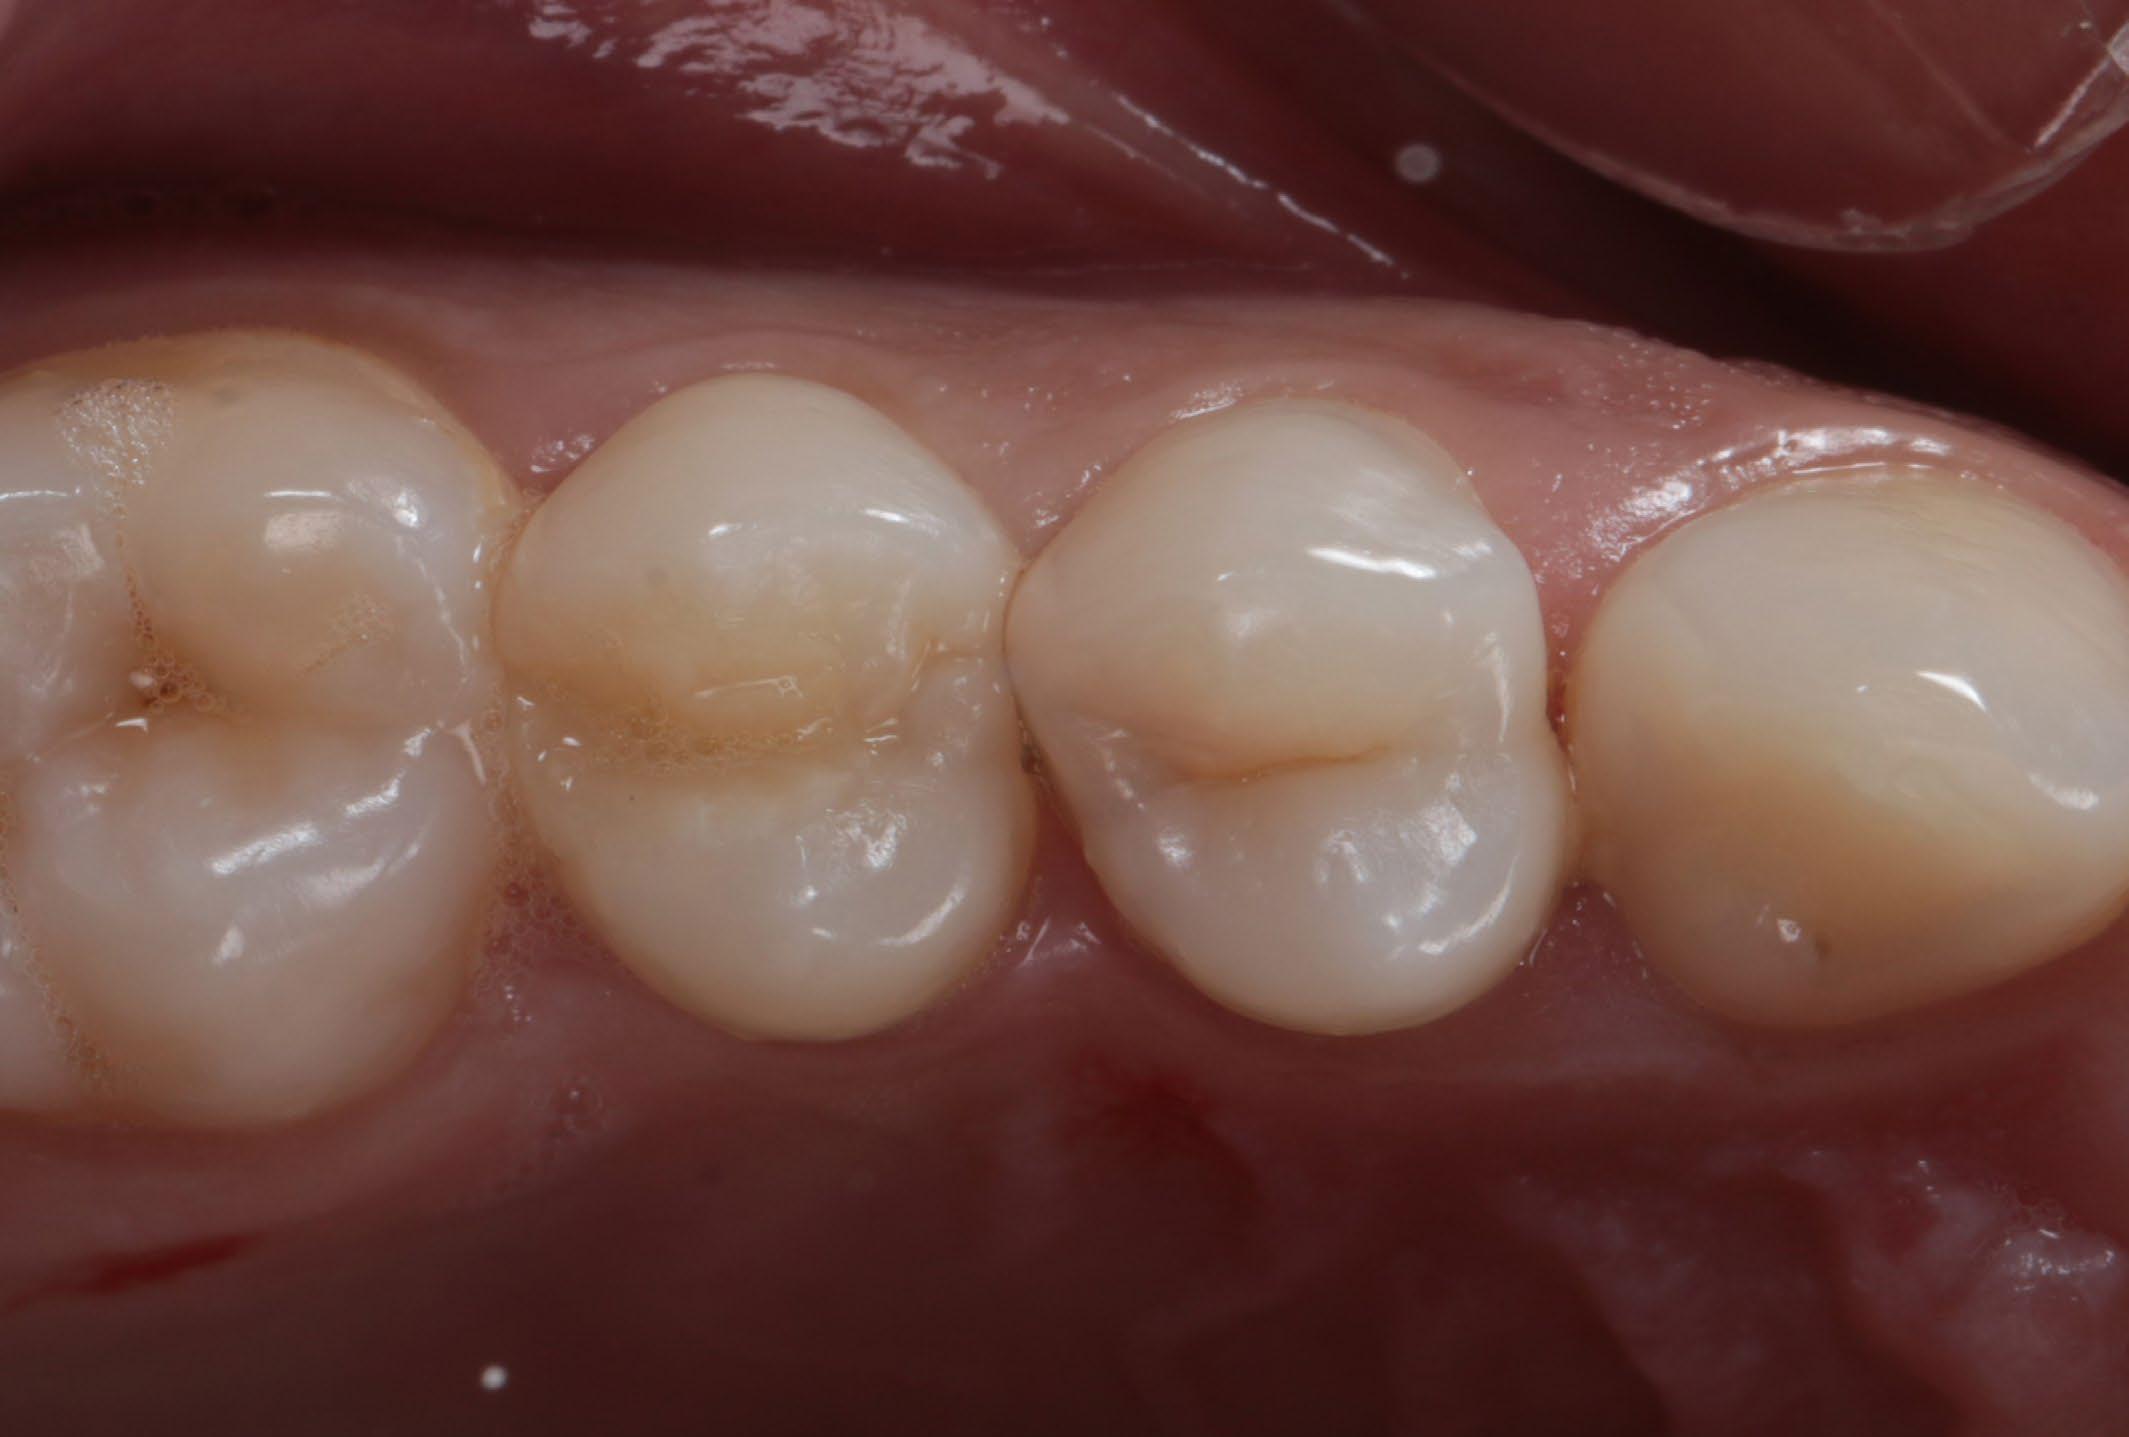

Fig. 1: Initial situation. Fig. 2: X-ray showed hidden caries at the distal side of the upper first pre-molar. Fig. 3: Isolation with rubber dam. Fig. 4: Preparation. Hidden Proximal Caries | Posterior continues next page >>>